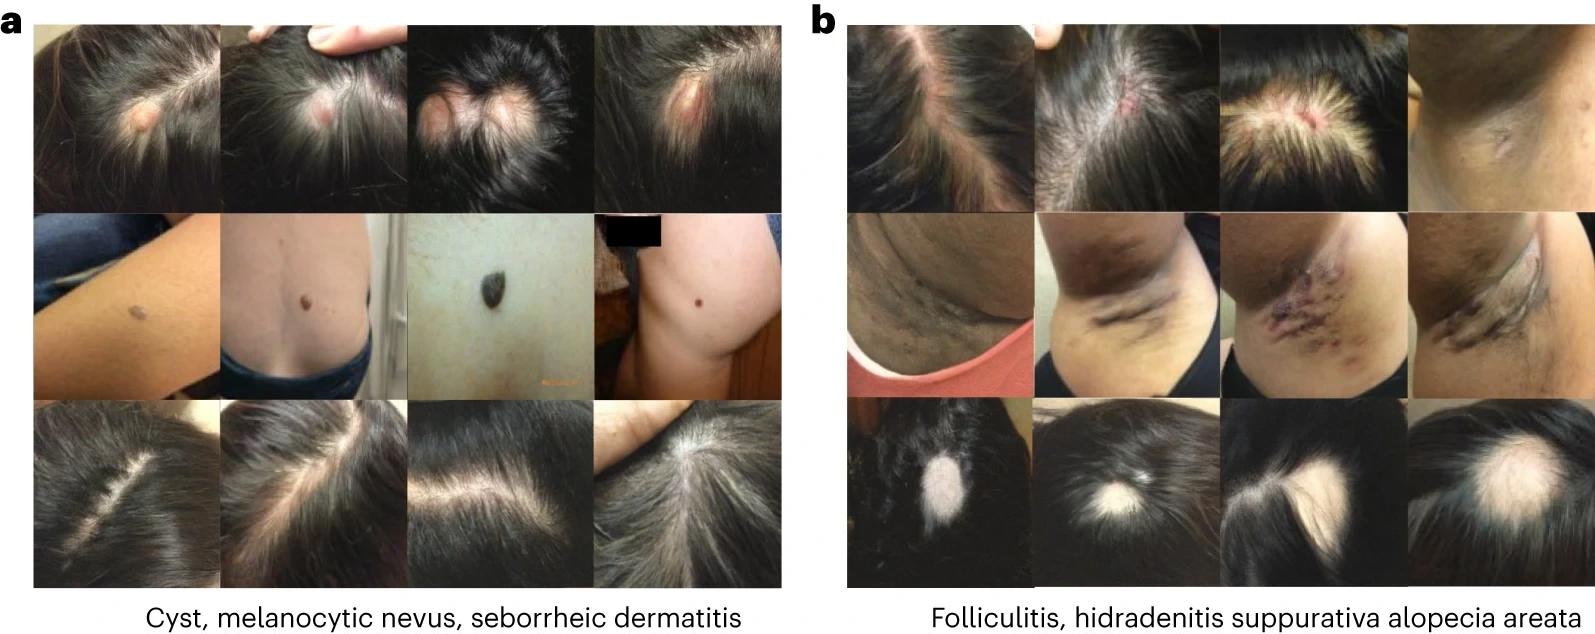

תמונות שנוצרו במסגרת דרמטולוגיה. כל שורת תמונות מתאימה למצב אחר. אתמונות שנוצרו עבור ציסטה, nevus melanocytic ו-seborrheic dermatitis. בתמונות שנוצרו עבור דלקת זקיקים, hidradenitis ו-alopecia areata.

תמונות שנוצרו במסגרת דרמטולוגיה. כל שורת תמונות מתאימה למצב אחר. אתמונות שנוצרו עבור ציסטה, nevus melanocytic ו-seborrheic dermatitis. בתמונות שנוצרו עבור דלקת זקיקים, hidradenitis ו-alopecia areata.

התניית תווית ומאפיינים שיפרו את הרגישות האבחונית בסיכון גבוה ב-27% והגדילו את ה-OOD ב-63.5%, מה שצמצם את פער ההוגנות ב-7.5×. השיטות הדרמטולוגיות יצרו תמונות מציאותיות וקנוניות שלכדו מאפיינים של מחלות רבות, כולל מקרים נדירים. תמונות סינתטיות הפחיתו גם מתאמים כוזבים וייצוגים דחוסים, והפחיתו את התלות של המודל במתאמי OOD שאינם ניתנים להכללה ובפרטים חסרי שירות.